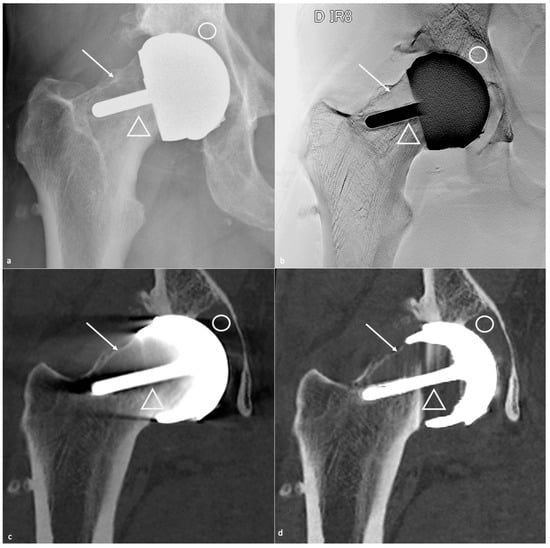

- Sutphen, S.A.; Lipman, J.D.; Jerabek, S.A.; Mayman, D.J.; Esposito, C.I. Treatment of Recurrent Dislocation after Total Hip Arthroplasty Using Advanced Imaging and Three-Dimensional Modeling Techniques: A Case Series. HSS J. 2020, 16, 245–255. [Google Scholar] [CrossRef]